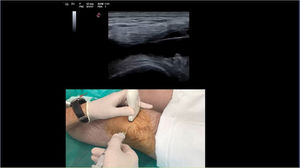

A lo largo del recorrido del procedimiento el participante debe ir resolviendo las cuestiones que se le van planteando, algunas de conocimiento y otras de toma de decisiones (fig. 6). Utilizamos imágenes del líquido sinovial en jeringas, de ecografías, así como de diversas preparaciones en portaobjetos para identificar cristales mediante el microscopio óptico y de cultivos celulares para el análisis microbiológico (fig. 7).